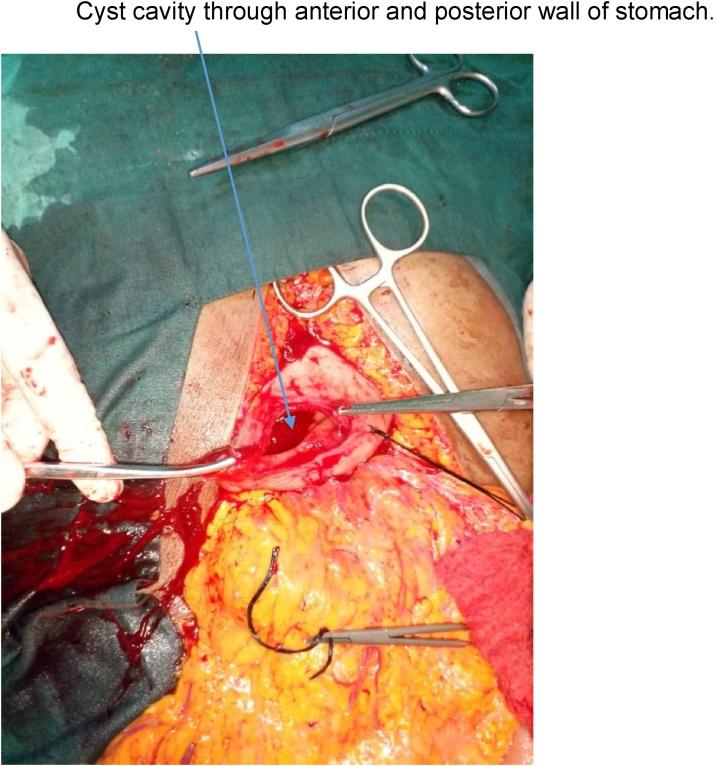

Two female patients aged 22 years and 65 years respectively, and an 11-year-old boy presented with giant pancreatic pseudocysts (>10 cm in diameter each) to our unit and were successfully managed. They all underwent exploratory laparotomy and cysto-gastrostomy with good outcome.

两名分别为22岁和65岁的女性患者以及一名11岁男孩因胰腺巨大假性囊肿(直径均>10 cm)前来我院就诊,并成功接受治疗。他们均接受了剖腹探查术和囊肿胃吻合术,效果良好。